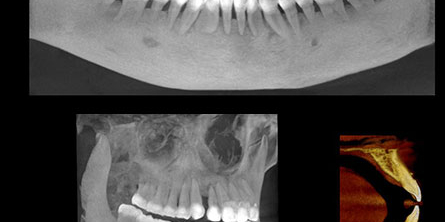

More detail, more confidence

70μm resolution @ 4x3cm

Superior image processing technology